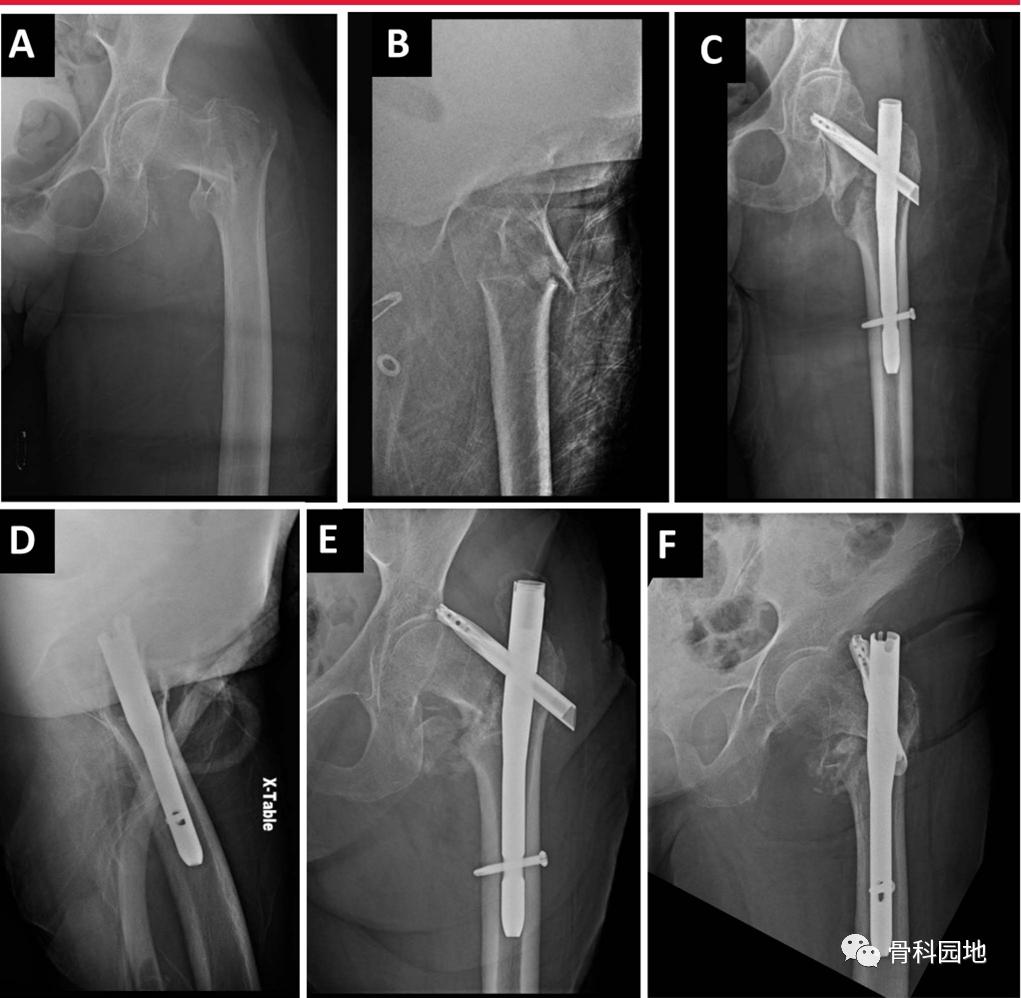

多种辅助技术和工具可用于骨折复位,包括尖头复位钳、环扎钢丝、骨钩、球钉推杆、共线钳和单皮质钢板(下图。

A和B,损伤AP和右侧髋侧位x线片显示髋粗隆粉碎骨折。C,透视图像显示用于复位的多点复位钳和环扎钢丝。D, AP骨盆术后显示股骨转子周围骨折复位良好。E, AP术后图像显示骨折复位良好,重建钉置入。F,侧位图像显示髋关节转子周围骨折位置良好,复位良好。G,显示辅助经皮复位工具,包括(从R到L) Cobb,骨钩,共线钳和球钉推杆。